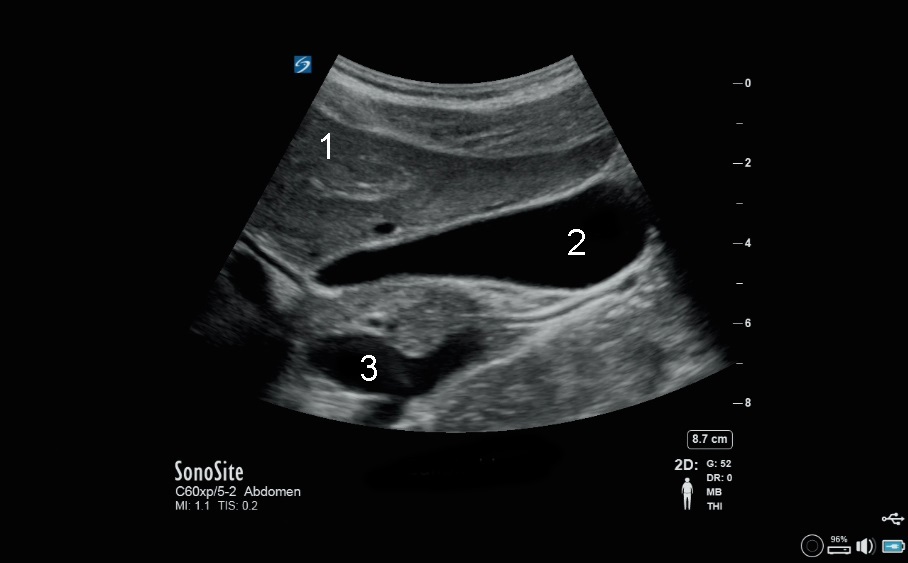

胆囊 X-Porte 图像

肝脏

胆囊 (GB)

下腔静脉 (IVC)